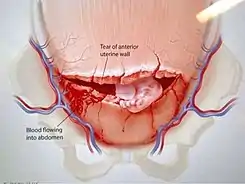

Ruptura uterina

La ruptura o rotura uterina es la solución de continuidad no quirúrgica del útero, que ocurre por encima del cuello y en gestaciones avanzadas, porque habitualmente las del cuello reciben el nombre de desgarros y las del cuerpo, que se producen en gestaciones pequeñas, se denominan perforaciones uterinas. Es una complicación muy grave y se acompaña de alta mortalidad materna y perinatal.

Rotura uterina consumada. Después de los síntomas y signos que se observan en la inminencia de rotura uterina antes descrita, en el clímax de una contracción enérgica, la paciente se queja de dolor agudo y cortante en el abdomen inferior y, a menudo, puede sentir que "algo se ha roto" dentro de ella.

En ese momento puede sentir movimientos fetales muy activos que al morir el feto cesan totalmente. Como consecuencia de la rotura, aparece un sangramiento vaginal rojo radiante que puede no ser muy intenso, porque la mayor cantidad de sangre está en la cavidad peritoneal, y por eso llama la atención el mal estado de la paciente que no se corresponde con el aparente escaso sangramiento.

Las partes fetales se palpan con mucha facilidad porque el feto puede estar totalmente libre en la cavidad peritoneal. Por eso también la presentación que se había observado en el canal pélvico, asciende al salir el feto hacia la cavidad peritoneal. El foco fetal es negativo.[1]